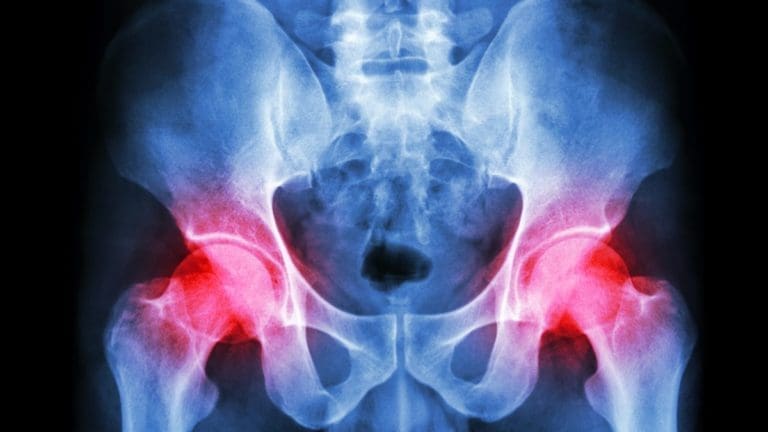

For individuals with pelvic pain, how does MET treatment strategies reduce muscle weakness in the hips region? Table of Contents ToggleIntroductionReferred Pain Symptoms Affecting The PelvisSciatica, Causes, Symptoms, & Tips- VideoMET Treatment Strategies For Pelvic PainMET Treatment...